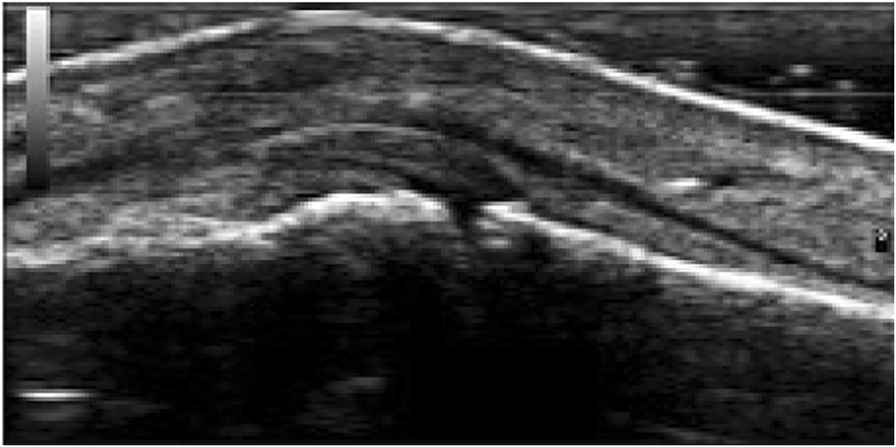

Fig. 1 (abstract P364).From: XXXV Brazilian Congress of Rheumatology (SBR 2018)Signs of paratendinitis of the extensor tendon of the third left fingerBack to article page